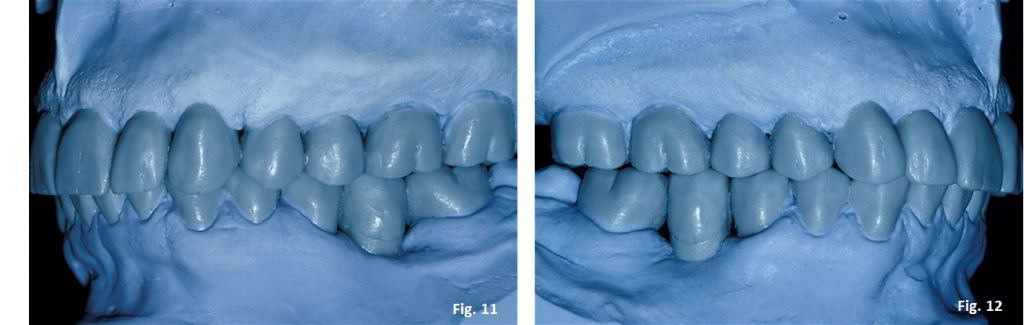

Once the maxillary occlusal plane has been waxed, the table can be removed and the lower model replaced to finish the wax-up. (Figs. 11-12)